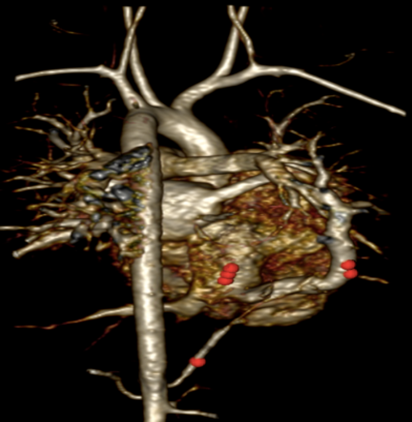

Routine laboratory analysis, including a complete blood count and metabolic panel, is normal. A postero-anterior chest roentgenogram is shown in Figure 1. Chest computed tomography (CT) without IV contrast (Figure 2), and gadolinium enhanced magnetic resonance angiogram (Figures 3 and 4) are also obtained. A decision is made to perform a cardiac catheterization (Figures 5 and 6) for further evaluation.

Figure 5

The red arrow (Figures 7, 8, 9, and 11) shows a large scimitar vein. Chest CT (Figure 8) shows partial anomalous pulmonary venous return from the right lower pulmonary vein into the inferior vena cava (IVC) and right-sided pulmonary hypoplasia with consequent dextro-position of the heart into the right hemithorax. The gadolinium-enhanced angiography cardiac magnetic resonance imaging (MRI) (Figure 9) with three-dimensional reconstruction (Figure 10, Video 1) confirms the diagnosis, which shows aortopulmonary collaterals from the descending abdominal aorta to the right lower lung lobe (one dot), large anomalous pulmonary vein, the scimitar vein (two dots), draining the right lower lung to the IVC (three dots). The right heart is within normal limits for size.

A cardiac catheterization is performed. Right pulmonary artery and descending aorta injections (Figures 11 and 12) show a large scimitar vein and aortopulmonary collaterals to the right lung (orange arrow, Video 2). Coil occlusion of the aortopulmonary collateral is done at the time of the cardiac catheterization. Qp:Qs was 1.3:1 on both MRI and on cardiac catheterization.